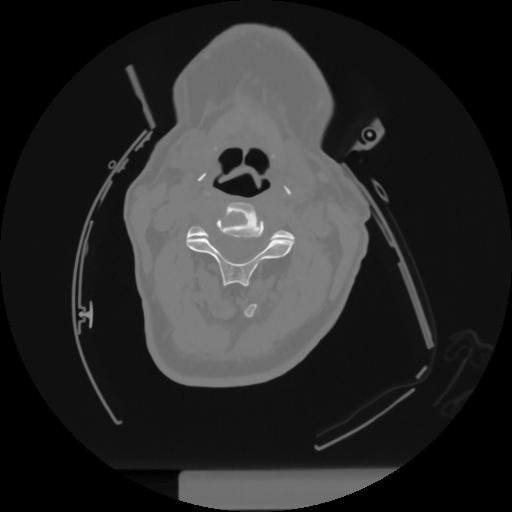

12 P.BLANDAS,,Vol,0.5,P.BLANDAS,,